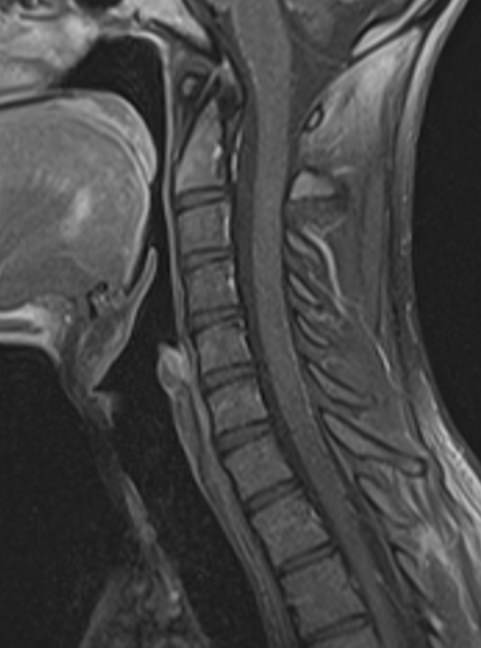

Магнитно-резонансная томография является современным, высокоинформативным и доступным методом обследования позвоночника. МРТ позволяет оценить состояние костных структур позвонков, спинного мозга, нервных корешков и окружающих мягких тканей. С помощью МРТ можно диагностировать грыжевые выпячивания межпозвонковых дисков, степень их воздействия на нервные корешки и спинной мозг.

Но несмотря на высокую диагностическую ценность магнитно-резонансной томографии, в некоторых случаях для улучшения визуализации патологических очагов дополнительно применяется контрастное усиление. В частности, при подозрении на опухоли позвоночника или спинномозгового канала, для оценки активности очагов демиелинизации спинного мозга, требуется внутривенное введение контраста.

В клинике «Доступная медицина» выполняется МРТ различных отделов позвоночника. В зависимости от уровня поражения можно провести МР томографию шейного отдела, грудного отдела, пояснично-крестцового отдела позвоночника и копчика.